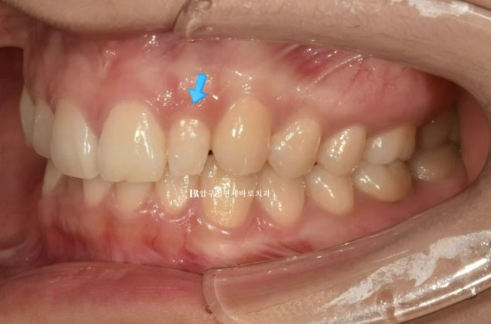

23.10

파란 화살표는 왜소치이고 앞니를 제외한 뒤쪽 어금니 배열은 양호합니다.

덧니나 왜소치가 있는 경우라면 앞니 중심선이 그쪽으로 쏠려있는 경우가 많습니다.

앞니 부분교정에서는 중심선을 포기하는 경우가 많지만 이 왜소치를 정상 사이즈로 회복하는 라미네이트 치료를 하게 되면

중심선까지 맞춰서 마무리가 가능합니다.

따라서 앞니 부분교정 후에 왜소치 무삭제 라미네이트 치료도 추천드렸습니다.